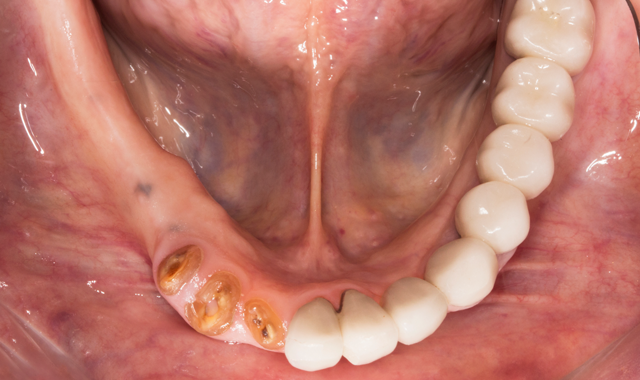

A 70-year-old patient presented with fractured teeth and multiple failing restorations (Fig. 1-2). It was determined that the mandibular teeth were not restorable. The treatment plan was for a mandibular fixed detachable prosthesis with five implants. Due to patient’s finances, the maxillary arch will be restored after the mandibular arch is finished.

Fig. 1

Fig. 2